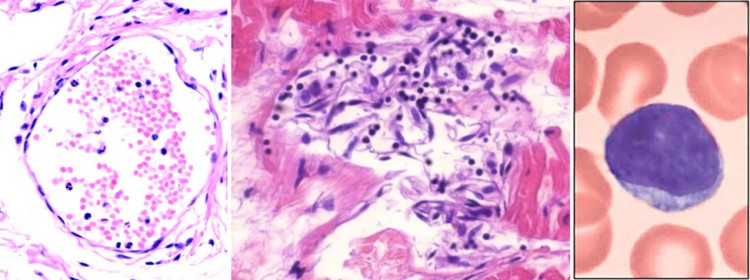

Figure 1. The Schwab paper shows that the COVID vaccine causes antigen to be expressed by the heart causing the body to attack the heart leading to death. It’s that simple.

“Our findings establish the histological phenotype of lethal vaccination-associated myocarditis.”

In plain English, it means that “the COVID shot kills people by damaging their heart.”

They found heart damage consistent with vaccine-induced myocarditis in all 5 cases that they examined in depth.

“During the last 20 years of autopsy service at Heidelberg University Hospital we did not observe comparable myocardial inflammatory infiltration.”